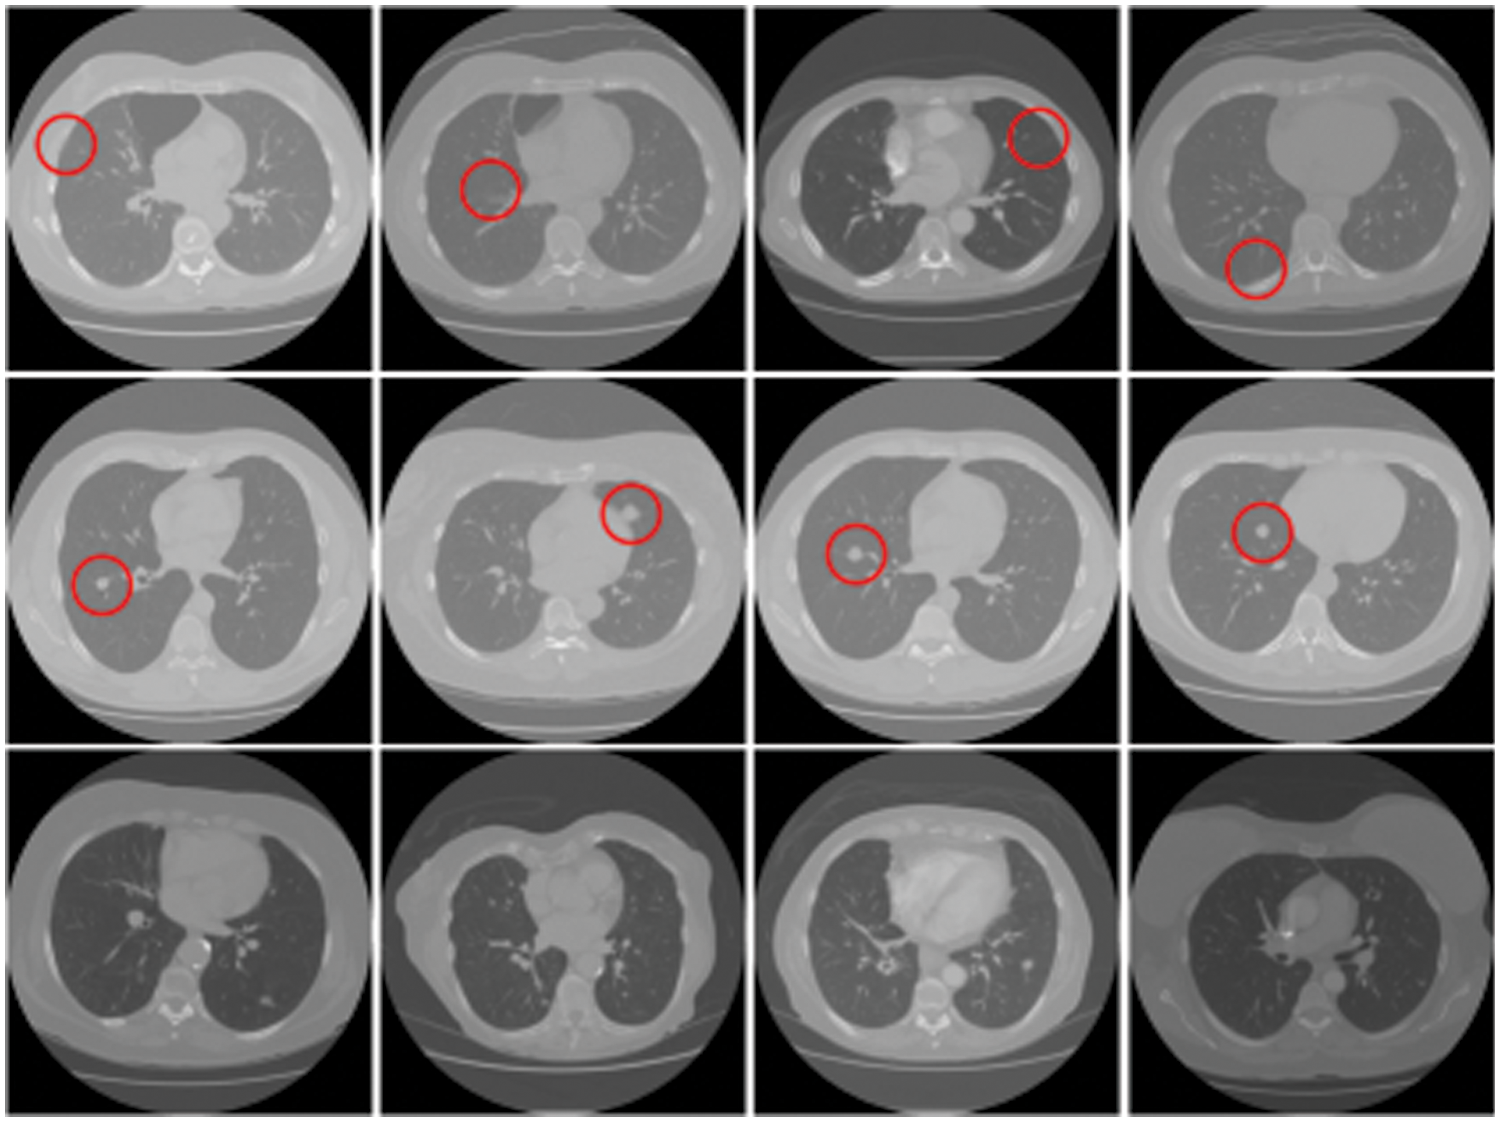

More constructively, deep fake technology is also used in healthcare. One potential route for generating deep fakes in medical scans is associated with injecting and removing tumors, as shown in Fig. 2. Most medical images are grayscale and low resolution, making it more difficult for people and algorithms to detect manipulation. This is in contrast to images of nature scenes, which often have high-resolution color and texture details. If a medical deep fake goes undetected, it might cost the hospitals a lot of money or someone’s life.

Figure 2: Tampered raw CT-scan images. Row 1: Removed samples, Row 2: Injected samples, Row 3: Untampered samples